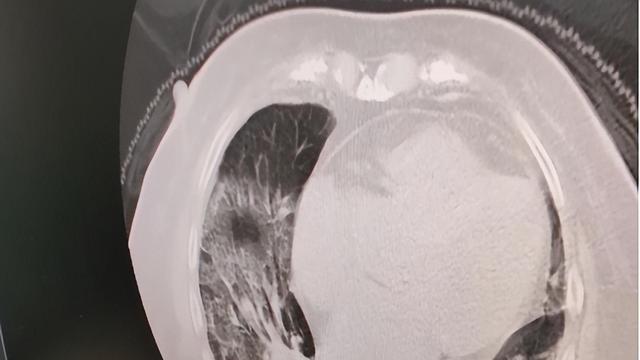

文章图片